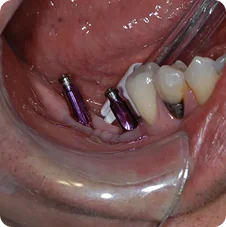

Post-operative Implant Placements

Impressions #18, 19 and 20

Impressions #30 and 31